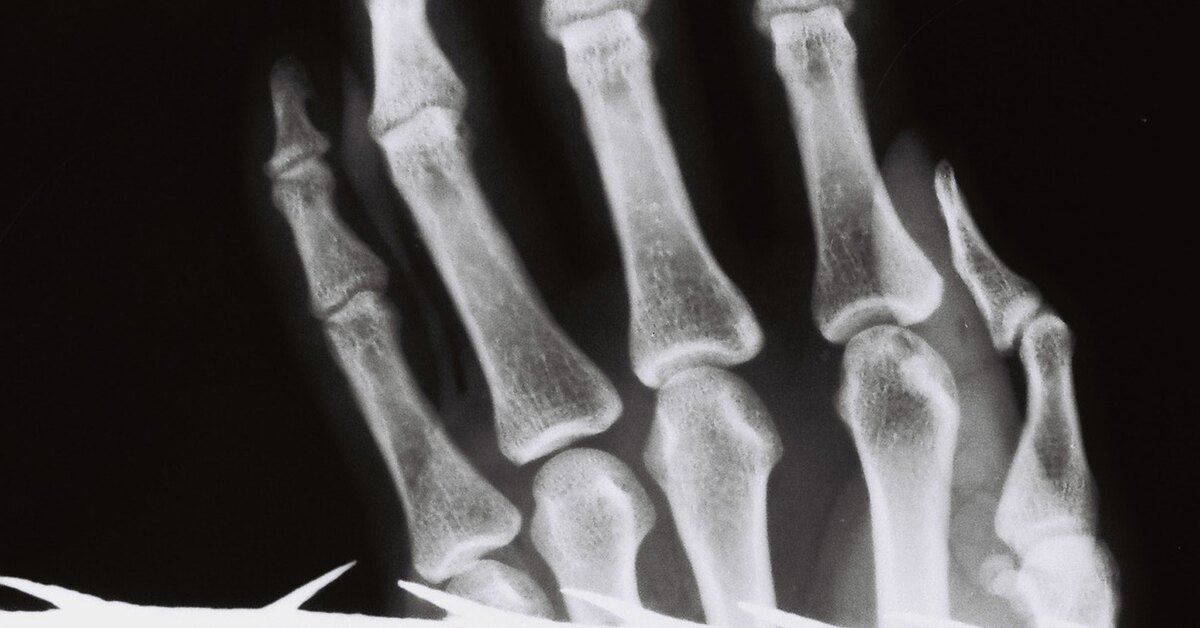

ИРАН, 1979 ГОД

Ступня 14-летней девочки с отмершими фалангами второго и третьего пальцев. За то, что она вышла на улицу с накрашенными ресницами и губами, бойцы революционной гвардии зажали ее ноги в тиски. Пальцы рук и ног обладают повышенной чувствительностью, и палачи часто выбирают их объектом пыток. При этом нет риска, что жертва умрет.